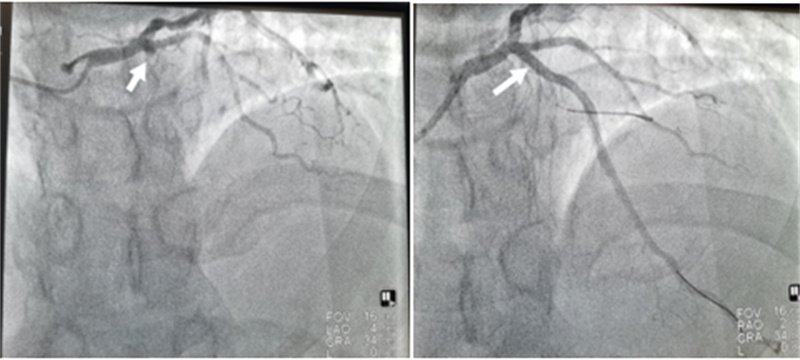

石琳与马斌医生共同为患者进行了冠脉造影检查,术中发现前降支开口100%闭塞并植入支架一枚,从接诊到支架植入仅耗时四十分钟。术后患者恢复良好,目前已康复出院。